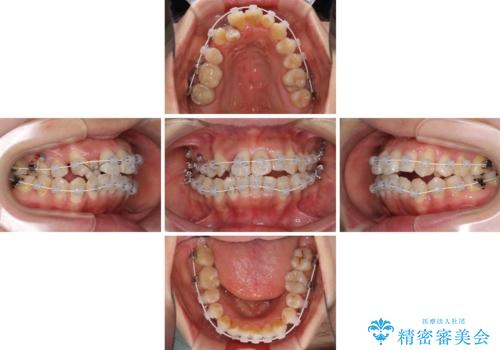

上顎骨を急速拡大装置により拡大し、ワイヤー装置による抜歯矯正治療を行うこととしました。

治療途中、長期間海外旅行をされたり、帰国後には遠方へ転居されたりと、治療期間が伸びましたが、2年強で治療を終えることができました。